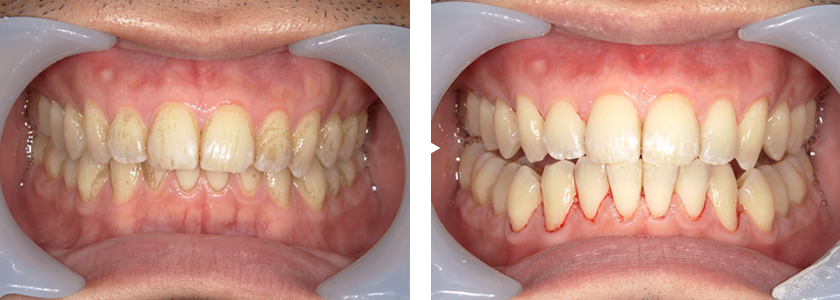

審美歯科

審美歯科は、単なる歯の健康維持だけでなく、「歯を白くしたい」「歯並びをきれいに整えたい」などの見た目の美しさを追求すし、機能面の改善も併せて整えることを目的とする歯科治療です。見た目の美しさを追求する歯科医療の分野です。患者様に、自分に自信が持てる健康的で美しい笑顔をもたらすことです。

エアフロー

歯の着色汚れを落とし、本来の色に近づけるだけではなく、口全体の汚れを短時間で効率よく落とします。

歯や歯茎に負担が少なく、痛みもほとんどありません。

虫歯や歯周病の予防に効果的で、歯の汚れを落とし口の中をすっきりとさせます。